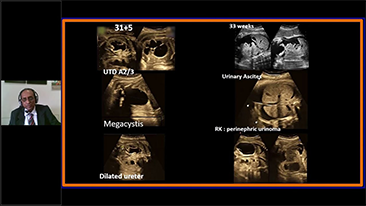

Wawasan